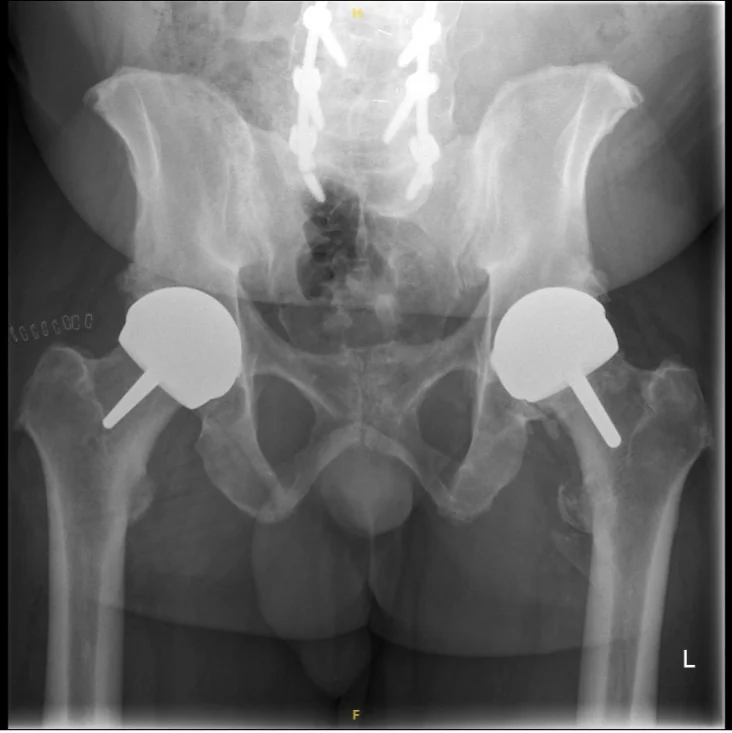

Surgical Images & X-rays

Mr Hussain selects the most appropriate implant for each patient based on their anatomy, bone quality, activity goals, and gender. He is one of few UK surgeons offering both metal-on-metal and ceramic-on-ceramic resurfacing options.

A proven metal-on-metal resurfacing system with excellent long-term results. Used primarily in male patients with adequate femoral head size. Well-established track record with robust clinical evidence.

A ceramic-on-ceramic resurfacing implant suitable for both male and female patients. Eliminates metal ion concerns associated with traditional resurfacing. Uses hybrid fixation with cement in the femoral component.

The latest generation ceramic-on-ceramic resurfacing implant with totally cementless fixation. Suitable for both men and women. Represents the cutting edge of hip resurfacing technology.